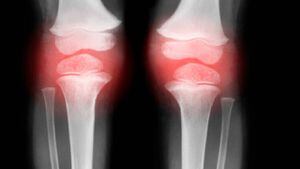

El dolor de rodilla es un padecimiento que puede afectar a personas de todas las edades. Es posible que sea resultado de una lesión, como una ruptura de ligamento o un desgarro de cartílago. Algunas afecciones médicas, como la artritis, la gota y las infecciones, también en ocasiones lo provocan, según el instituto Mayo Clinic.

La ubicación e intensidad de la molestia puede variar según la causa del problema. Los signos y síntomas que en algunas oportunidades acompañan el dolor de rodilla son:

- Inflamación y rigidez

- Enrojecimiento y temperatura al tacto